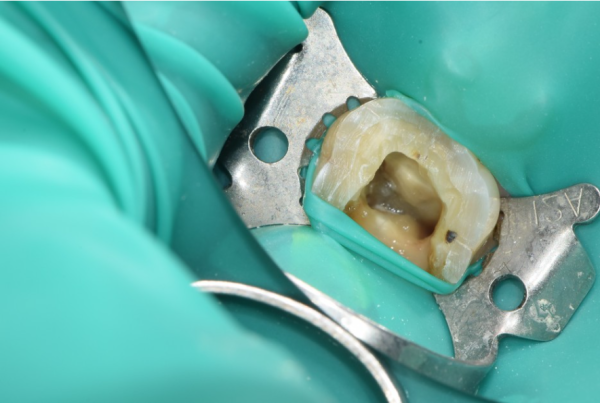

이 환자분의 경우에는 이미 상당한 통증이 있는 상태였습니다.

In this patient's case, there was already considerable pain.

위의 사진을 보면, 법랑질을 넘어 상아질까지 넓게 충치가 있어

치수 가까이 충치가 진행된 상황입니다. 때문에 신경치료 필요한 상황입니다.

If you look at the picture above, there's a wide cavity beyond enamel to ivory.

The cavity has progressed close to the size. Therefore, neurosurgery is necessary.